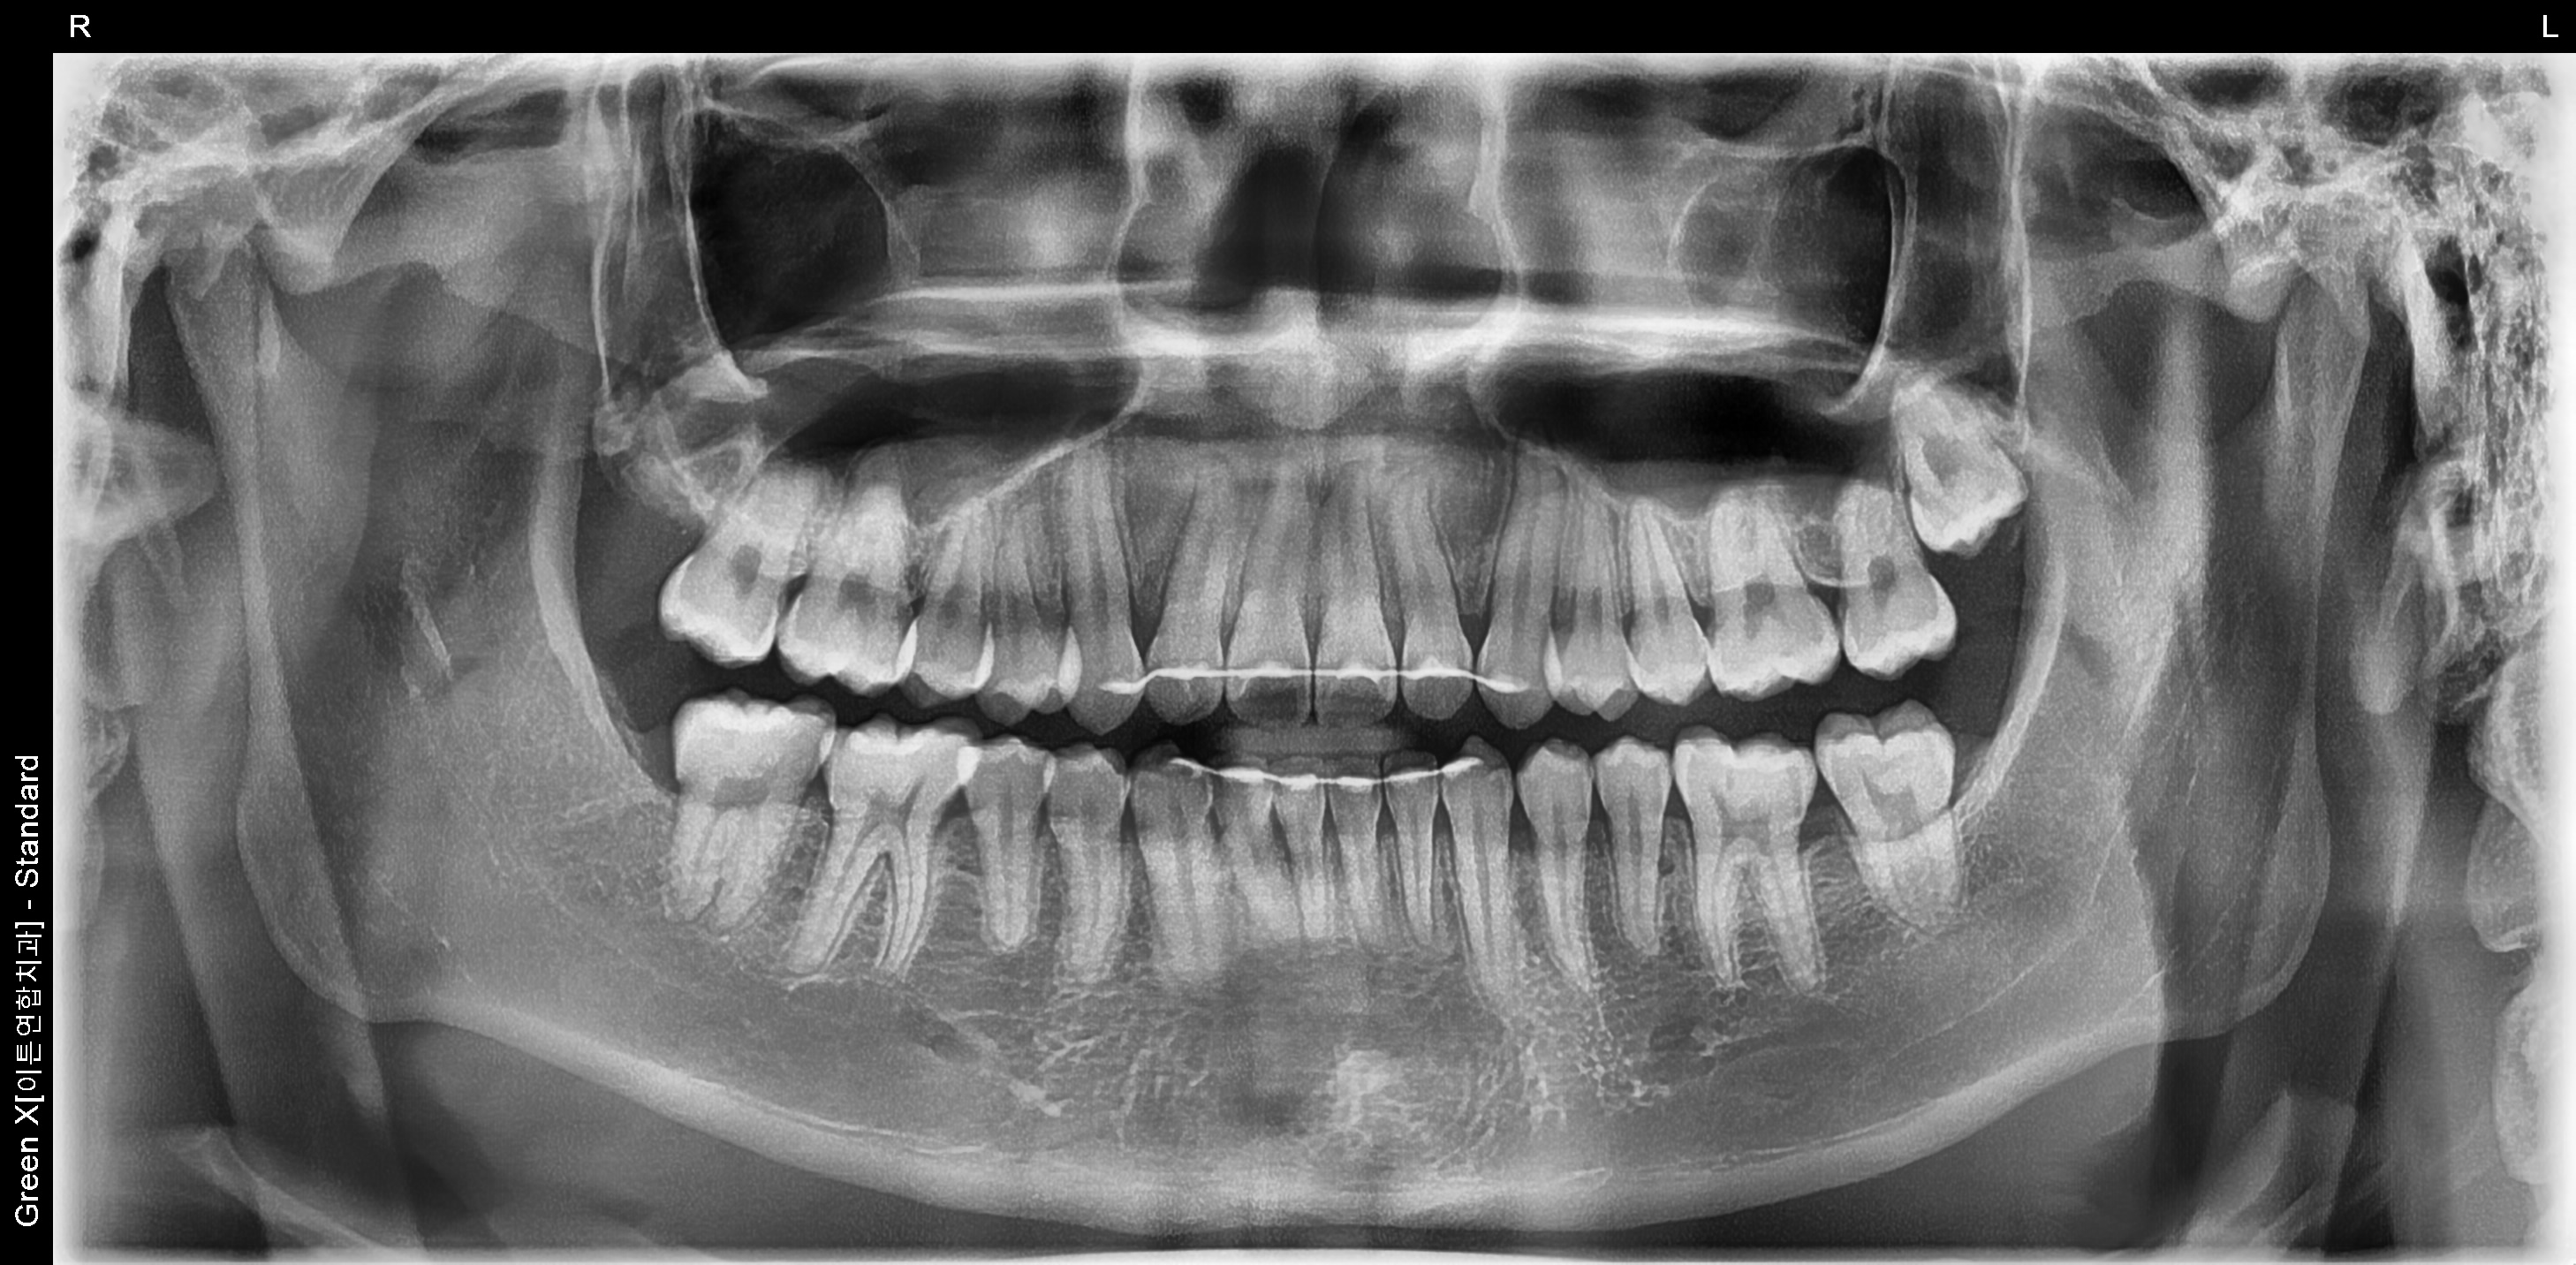

환자명 : 이OO

2025.05.26 업데이트

수술 후 촬영일자 : 2025.04.04

*해당 이미지는 의료법 제57조 동법 시행령을 준수하여 본원에서 직접 촬영했습니다.

치료 전후 사진은 환자분의 동의하에 동일 조건, 인물을 촬영 한 사진을 인위적인

수정 없이 사용해 일반적인 치과 치료 정보를 제공할 목적으로 게시되었습니다.

모든 시술은 개인에 따라 차이가 있을 수 있으며, 부작용이 발생할 수 있으니 의료진과

충분한 상담 후 진행하셔야 합니다.